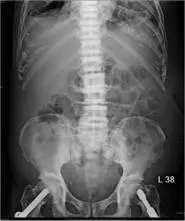

75 歲男性,副甲狀腺素血液濃度上升,腹部 X光檢查如附圖,其脊椎骨的變化為何?

腹部 X 光(前後位)顯示腰椎及骨盆影像,重點發現如下:

- 脊椎椎體(vertebral bodies):多節腰椎椎體呈現交替帶狀高密度影,椎體上下緣終板(endplates)明顯硬化(sclerotic),而椎體中央相對透亮(lucent)。這種「密—透—密」交替的橫帶狀外觀酷似橄欖球衫(rugby jersey)的橫條紋圖案,即為經典的 Rugger Jersey Spine 表現。

- 多節連續受累:硬化改變見於多個連續椎體,而非局限於單一節段,與腫瘤轉移或感染的局灶性改變不同。

- 無椎間隙狹窄:椎間盤高度保留,可與感染(椎間盤炎)或退化性疾病區別。

- 骨盆骨:可見骨密度改變,與全身性代謝性骨病一致。

整體影像結合病史(75 歲男性、PTH 升高)高度支持**腎性骨病(renal osteodystrophy)**的診斷。